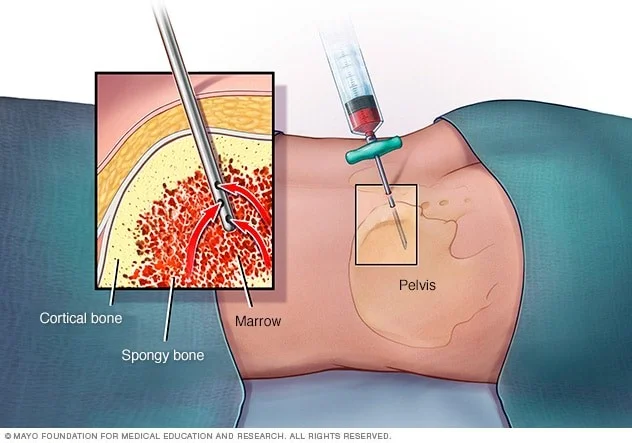

آسپیراسیون مغز استخوان (Bone marrow aspiration) و بیوپسی: این آزمایشها برای تشخیص HL استفاده نمیشوند اما ممکن است پس از تشخیص انجام شوند تا ببینند آیا لنفوم در مغز استخوان است یا خیر. آسپیراسیون مغز استخوان و بیوپسی معمولاً همزمان انجام میشود. نمونهها از پشت استخوان لگن (hip) گرفته میشوند اما گاهی اوقات ممکن است از استخوانهای دیگر نیز گرفته شوند.

در آسپیراسیون مغز استخوان، روی یک میز (به پهلو یا روی شکم) دراز میکشید. پس از تمیز کردن پوست روی لگن، پزشک با تزریق یک بی حس کننده موضعی (داروی بی حس کننده) پوست و سطح استخوان را بی حس میکند. این ممکن است باعث ایجاد یک احساس درد یا سوزش مختصر شود. سپس یک سوزن نازک و توخالی به داخل استخوان فشار داده میشود و از یک سرنگ برای مکیدن مقدار کمی از مغز استخوان مایع استفاده میشود. حتی با استفاده از داروی بیهوشی، اکثر بیماران هنگام بیرون کشیدن مغز استخوان درد مختصری دارند.

بیوپسی مغز استخوان معمولاً درست بعد از آسپیراسیون انجام میشود. یک تکه یا هسته کوچک استخوان و مغز با یک سوزن کمی بزرگتر که به داخل استخوان فشار داده میشود، برداشته میشود. بیوپسی ممکن است کمی درد نیز ایجاد کند.

به اکثر کودکانی که آسپیراسیون مغز استخوان و بیوپسی انجام میدهند، یا دارو داده میشود تا خواب آلود شوند یا تحت بیهوشی عمومی قرار میگیرند تا در حین انجام آن بخوابند.